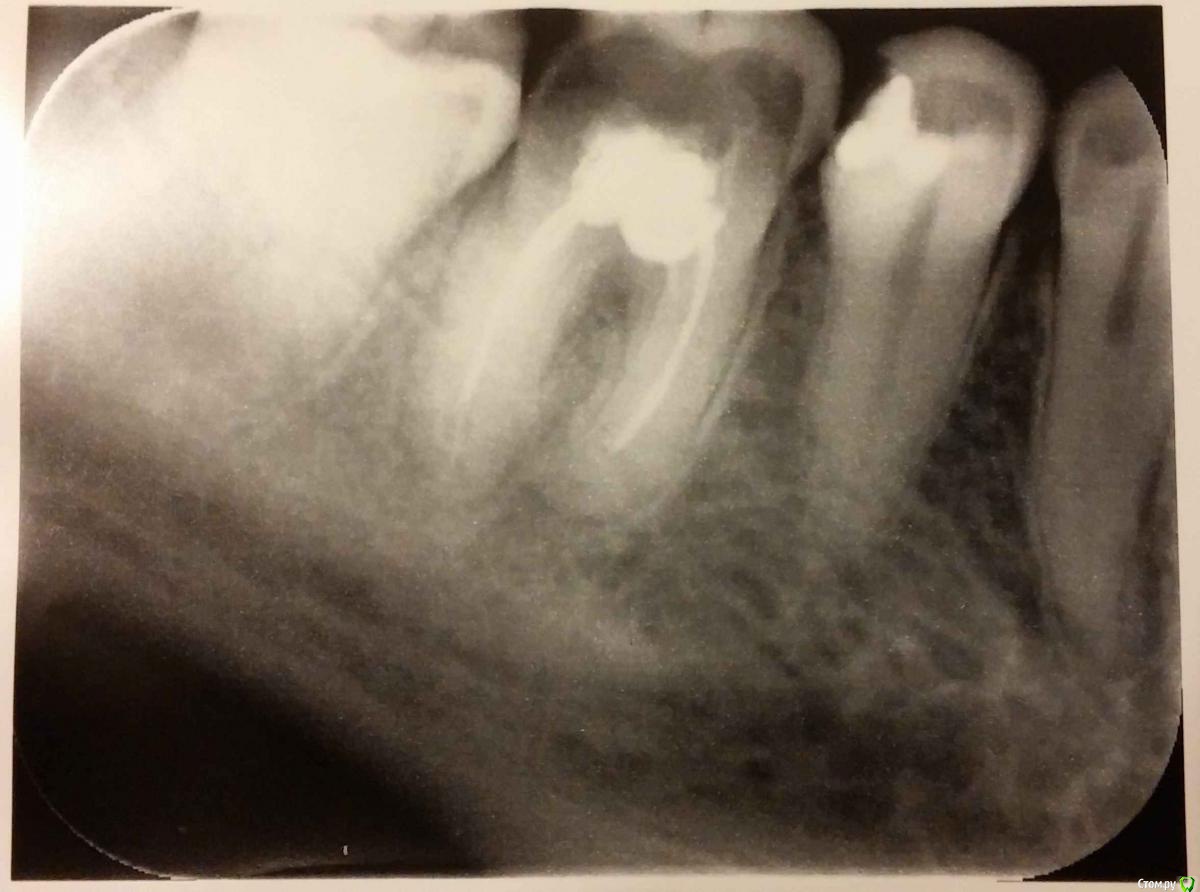

St. Опубликовано 8 декабря, 2015 Поделиться Опубликовано 8 декабря, 2015 За пару дней справиться не получится.Если Вы планируете комплексно привести всё в порядок, то нужно сделать панорамный снимок, а лучше КТ(там будут видны все зубы, это позволит определиться с общими проблемами), далее в зубах в которых удалены нервы определяется качество лечения(т.е. смотрят где нужно перелечивать каналы), потом смотрят достаточно ли осталось от зуба, чтобы его восстановить.Чаще всего зубы без нервов необходимо покрывать коронками.Помимо этого в стндартное лечение входит гигиена и пломбирование кариеса, если необходимо. По Вашему снимку - каналы в зубе нужно перелечить, потом коронка, при условии что стенка скололась неглубоко. В соседнем зубе нужно заменить пломбу. 3 Ссылка на комментарий

red_butler Опубликовано 9 декабря, 2015 Поделиться Опубликовано 9 декабря, 2015 А я вижу зуб который нужно удалять Ссылка на комментарий

red_butler Опубликовано 9 декабря, 2015 Поделиться Опубликовано 9 декабря, 2015 Поясните, плиз, что не так) Значительная степень разрушения зуба. Что вместо родного зуба делается? Имплантация. 1 Ссылка на комментарий

Гарриевич Опубликовано 9 декабря, 2015 Поделиться Опубликовано 9 декабря, 2015 Отлом стенки зуба язычно или щёчном не так критичен. Прогноз на зуб благоприятный. 1 Ссылка на комментарий

IvanK Опубликовано 9 декабря, 2015 Поделиться Опубликовано 9 декабря, 2015 А я вижу зуб который нужно удалятьтоже склоняюсь к Коллеге Сходите на очную консультацию, Врачей с Форума в Москве много 1 Ссылка на комментарий

Zlata-doctor Опубликовано 1 марта, 2016 Поделиться Опубликовано 1 марта, 2016 Бамбук, этот снимок не информативен. Вообще, рентгенологический снимок-дополнительный метод исследования, поэтому только по снимку ставить диагноз неправильно. Врачи высказала только предварительное мнение, очная консультация-обязательна.На два последних вопроса. которые вы задали, ответить будет затруднительно, так как нет объективных данных, КТ и неизвестны возможности ваших врачей, которых вы уже, по всей видимости, выбрали. Что они говорят? 1 Ссылка на комментарий